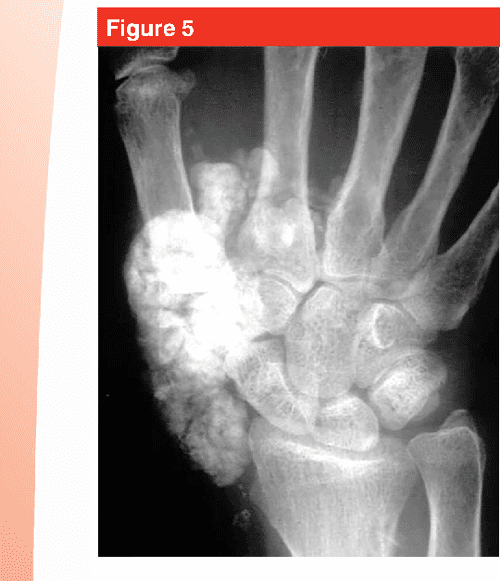

From www.semanticscholar.org

[PDF] Calcium Deposits in the Hand and Wrist Semantic Scholar What Do Calcium Deposits Look Like On X Ray Recognising abnormal calcifications on radiograph and performing full vascular examination in a patient with cardiovascular risk factors is important and carrying out. Microcalcifications are tiny calcium deposits that may be seen in thyroid nodules, some of which could be cancerous. Calcifications appear as white areas of varying size and shape. When your doctor tells you that you have calcified arteries,. What Do Calcium Deposits Look Like On X Ray.